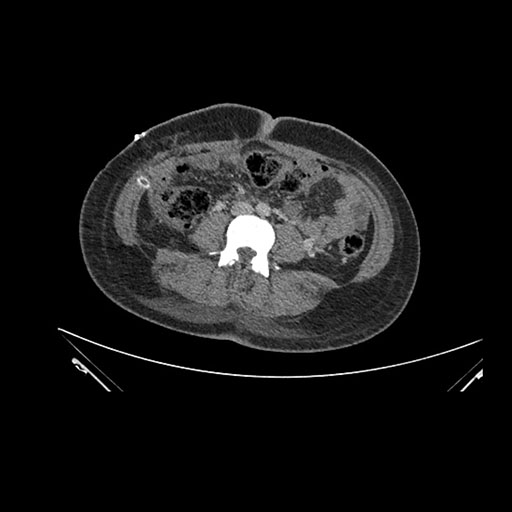

Imaging Analysis

Look through the patient's CT scan to identify any areas of concern for the necessary procedure.

Based on initial findings, which issue(s) would you be most concerned about?